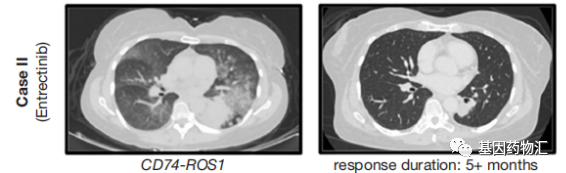

另一位60岁的患者,确诊时为右下叶肺腺癌,且颅脑成像提示了8个颅内病灶。二代测序提示了CD74-ROS1(C6:R33)融合突变,同样在第一代ROS1抑制剂的适应症范围内。但由于患者存在脑转移,因此一线治疗并没有选择克唑替尼,而是选择了入脑活性更强的恩曲替尼,每天600 mg剂量。

患者经历了一些不良事件,例如头晕、步态不稳和腹泻,因此将恩曲替尼的剂量减少至400 mg,疗效整体稳定,病灶以及颅内病灶持续缩小。